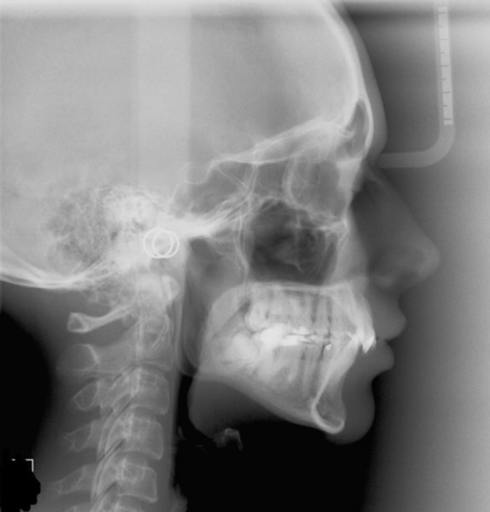

I am 24 years old and had braces when I was 10 years old until I was 12 years old. Since then my teeth have shifted and my lower jaw either did not grow as much as it should have or has moved backward. I have talked to an oral surgeon but am concerned that his suggestion will not work. I have an overjet of approximately 4mm or so and a small open bite (only because my teeth do not fit together when I bring them together). The OS recommended moving my upper teeth a little higher and forward. Would this not leave my lower jaw even further back? I do not see how moving my upper jaw would move my lower jaw at all. Please inform me of how this may work if it can.